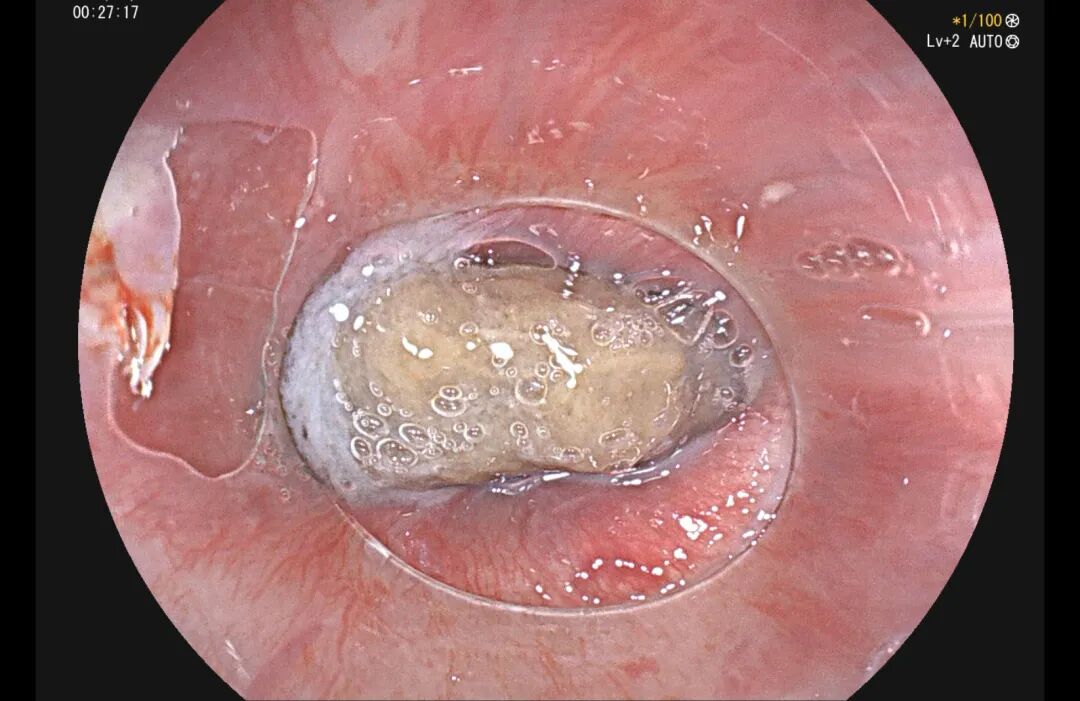

59 岁的沈阿姨,进食红枣后 4 小时突发咽痛、呕血,紧急来苏州京东方医院。影像检查显示:一枚长约 15 mm 的尖锐枣核横向嵌顿于食管颈段——这个位置紧邻颈部大动脉,若再深刺一毫米,或将引发致命性大出血。急诊胃镜下,医生小心翼翼取出枣核,沈阿姨才化险为夷。

放射科医生解读:

枣核两端尖锐,呈长梭形,在影像下清晰可见。嵌顿于食管颈段者,最危险的就是刺破毗邻的颈部大血管;而一旦进入肠道,在蠕动过程中枣核尖端如同「钻头」,极易穿透肠壁,且早期症状隐蔽,发现时往往已穿孔。